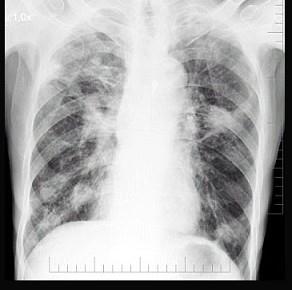

男性,72岁,感胸痛就诊,胸片检查如图,最可能的诊断是 ( )A.细支气管肺泡癌B.血行播散型肺结核C.肺转移瘤D.结核瘤E.胸腔积液

问题 男性,72岁,感胸痛就诊,胸片检查如图,最可能的诊断是 ( )

选项 A.细支气管肺泡癌 B.血行播散型肺结核 C.肺转移瘤 D.结核瘤 E.胸腔积液

答案 C